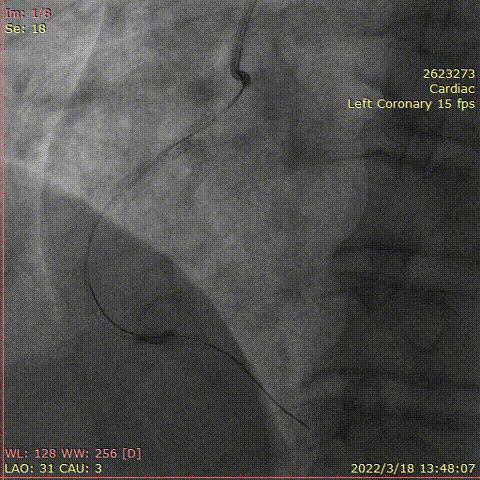

对右冠脉行介入治疗,钙化较重

对右冠脉行介入治疗,右冠脉中段预扩张后超声导管仍通过困难

选择1.5mm磨头高速旋磨

考虑指引导管支撑不佳,病变钙化重,血管迂曲,Telescope™导引延长导管支撑下,远段选择药物球囊PTCA

中断至近段置入支架